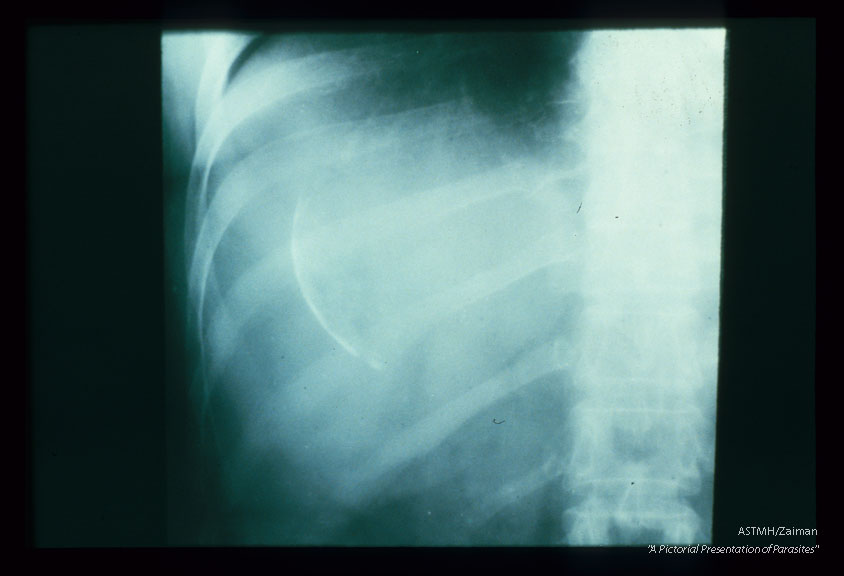

A cyst present in the upper portion of the right lobe of the liver is poorly calcified and presents only as a circumlinear white line.

Description: A cyst present in the upper portion of the right lobe of the liver is poorly calcified and presents only as a circumlinear white line.